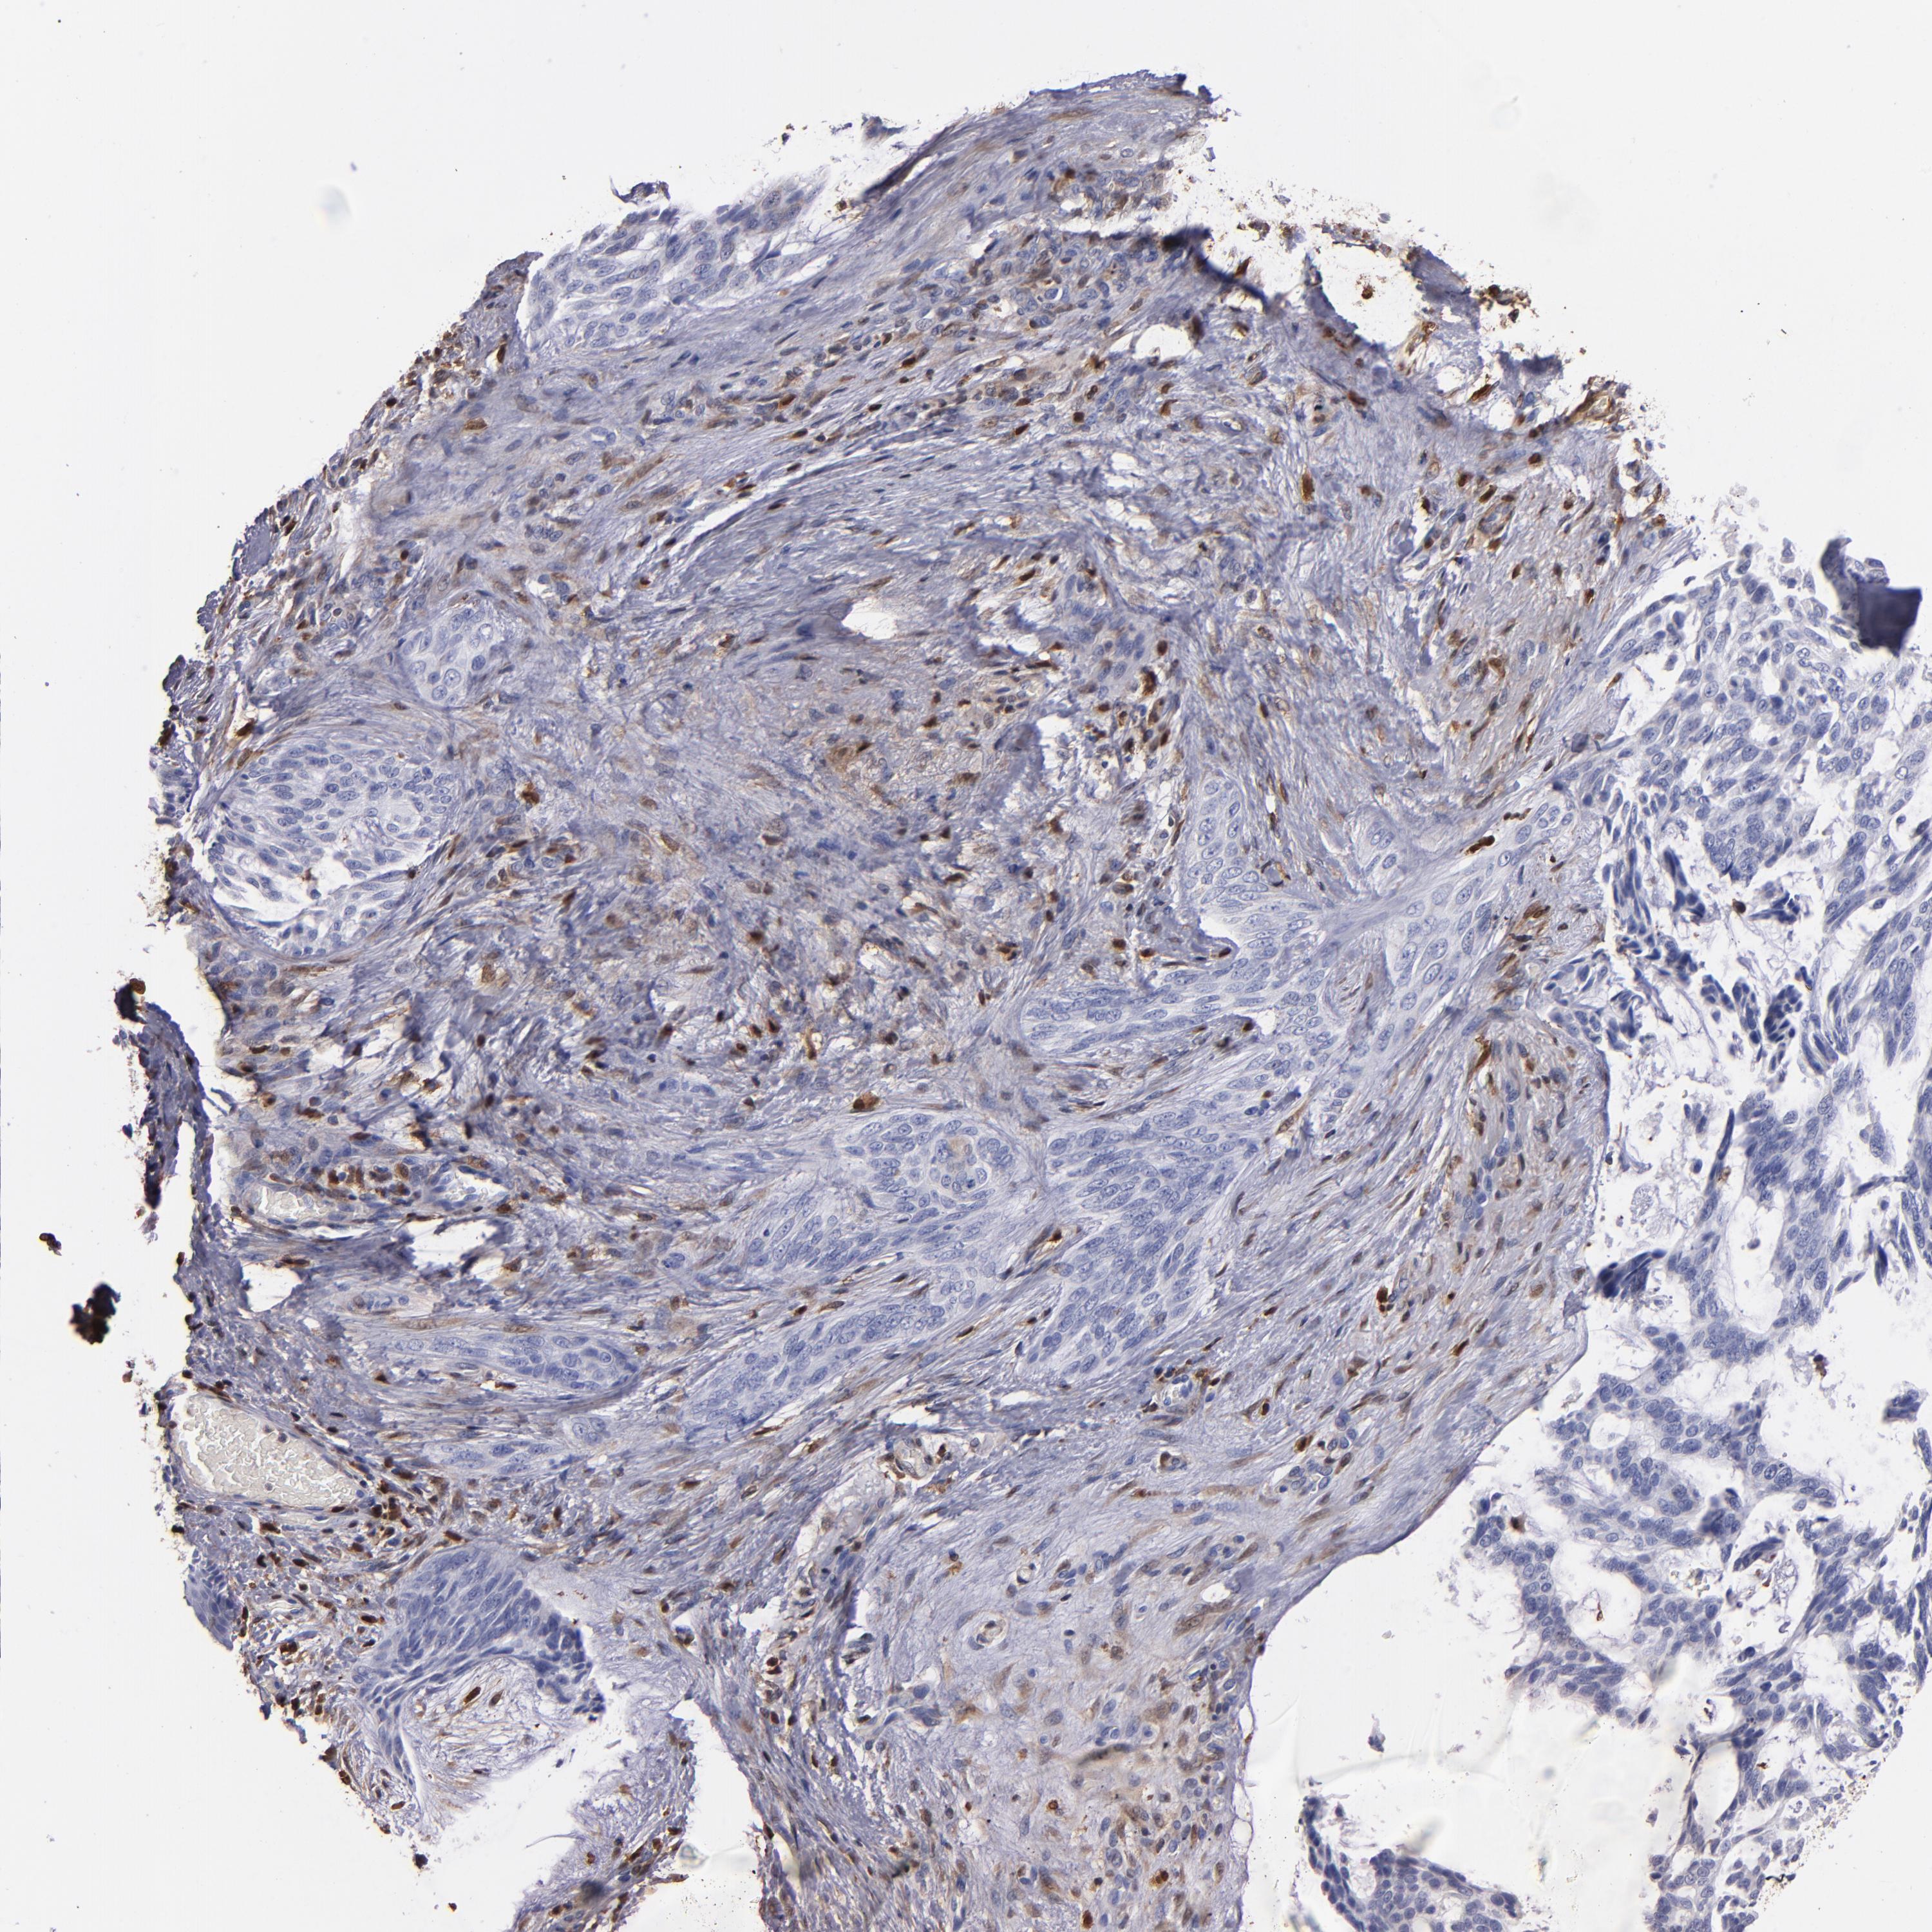

CANCER SKIN CANCER Show tissue menu

Basal cell and squamous cell cancer

SKIN CANCER - Protein expressioni

A mouse-over function shows sample information and annotation data. Click on an image to view it in a full screen mode. Samples can be filtered based on level of antibody staining by selecting one or several of the following categories: high, medium, low and not detected. The assay and annotation is described here.

Each image is clickable and will lead to virtual microscopy that enables deeper exploration of all samples and also displays staining intensity scores, fraction scores and subcellular localization as well as patient and tissue information for each sample.

HPA007973

CAB002618

CAB027387

CAB058698

CAB068227

CAB068228

Basal cell carcinoma

Squamous cell carcinoma, NOS

Squamous cell carcinoma, metastatic, NOS